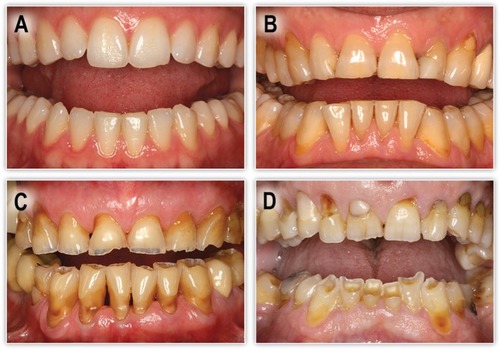

The revision of patients dental records indicated a variation in the degree of tooth wear between patients. Figure 2 represents clinical images of patients classified to have mild, moderate, and severe tooth wear. Different forms of tooth wear had been observed. Tooth attrition could be observed in Figure 2A and 2B, tooth erosion, and abfraction in Figure 2C and 2D.